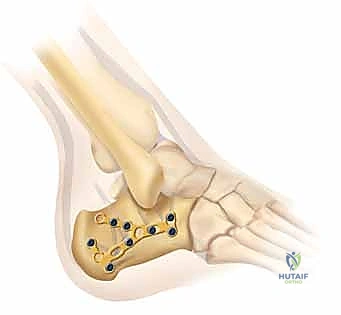

5. التثبيت النهائي باستخدام الشرائح والمسامير (Plating)

يتم وضع شريحة تيتانيوم (Titanium Plate) مصممة خصيصاً لتطابق الشكل التشريحي لعظم الكعب. يتم تثبيت هذه الشريحة بمسامير قوية لتوفير ثبات ميكانيكي صلب يسمح بالالتئام السليم ويمنع انهيار العظم مرة أخرى. في بعض الحالات التي يوجد فيها فراغ عظمي كبير، قد يستخدم الدكتور هطيف طعوماً عظمية (Bone Grafts) لملء الفراغ.

صور إضافية من داخل غرفة العمليات توضح دقة الإجراء

توضح الصور التالية مدى تعقيد الجراحة والدقة التي يتطلبها تثبيت عظم الكعب، والتي يعكسها التميز الجراحي للأستاذ الدكتور محمد هطيف: